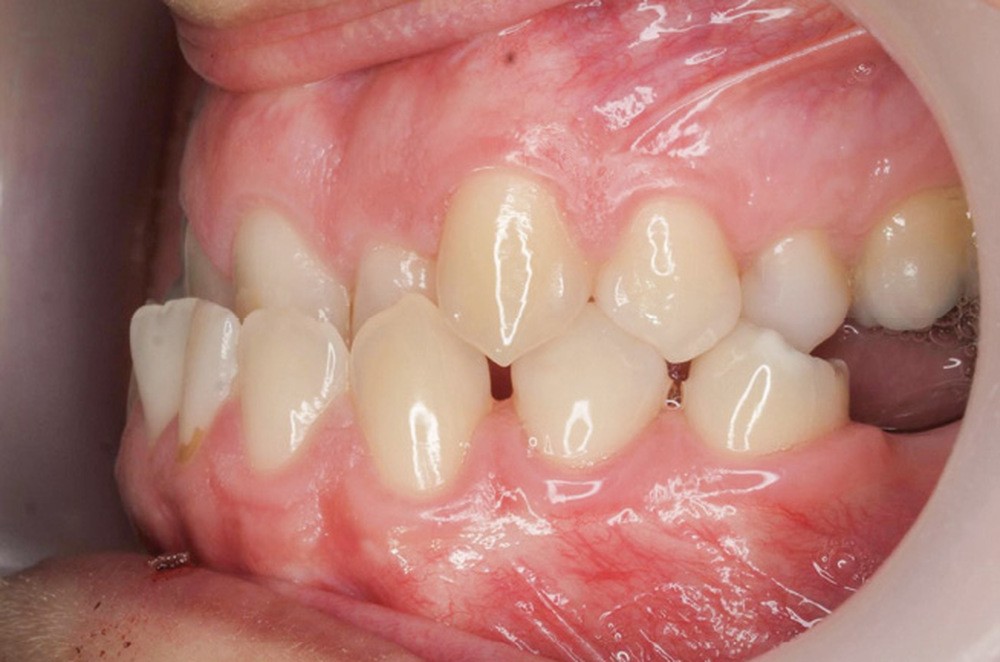

Diagnostic (fig. 1a-g)

La patiente présente une classe III squelettique dans un contexte hyperdivergent associée à une endoalvéolie maxillaire, un articulé inversé antérieur, une rétroversion incisive maxillaire, des rapports de classe I canine bilatérale, une absence de 16 et 36.

Au niveau esthétique, le profil est rectiligne. La lèvre supérieure est plus effacée, en retrait par rapport à la lèvre inférieure. De face et de profil, la mandibule paraît massive et le maxillaire effacé : le manque de soutien de la lèvre supérieure contribue à cette impression.

Le sourire est étroit, dégradé par les malpositions dentaires.

Au niveau fonctionnel, il existe un pro-glissement mandibulaire et un articulé inversé antérieur. Le profil téléradiographique montre en occlusion des rapports labiaux et un profil de classe III plus marqué que sur photographies.

Le traitement vise à améliorer les rapports squelettiques de classe III par repositionnement mandibulaire et correction de l’articulé inversé.

Au maxillaire, une expansion tridimensionnelle sera réalisée pour corriger la forme d’arcade et l’alignement.